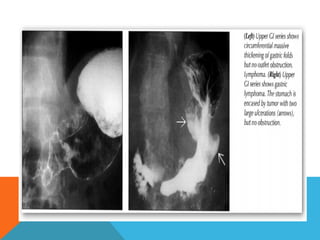

UPPER GI SERIES SHOWS MASSIVE NODULAR THICKENINGS

OF GASTRIC WALL/FOLDS; LYMPHOMA

UPPER GI SERIESSHOWS MASSIVE NODULAR THICKENINGS OF GASTRIC WALL/FOLDS; LYMPHOMA

Radiographic features Gastric lymphoma Fluoroscopy: Barium meal Appearances vary from normal, to grossly abnormal. Possible appearances include:  bull's eye appearance due to central ulceration  filling defects  thickened gastric rugae  linitis plastica

• 13.